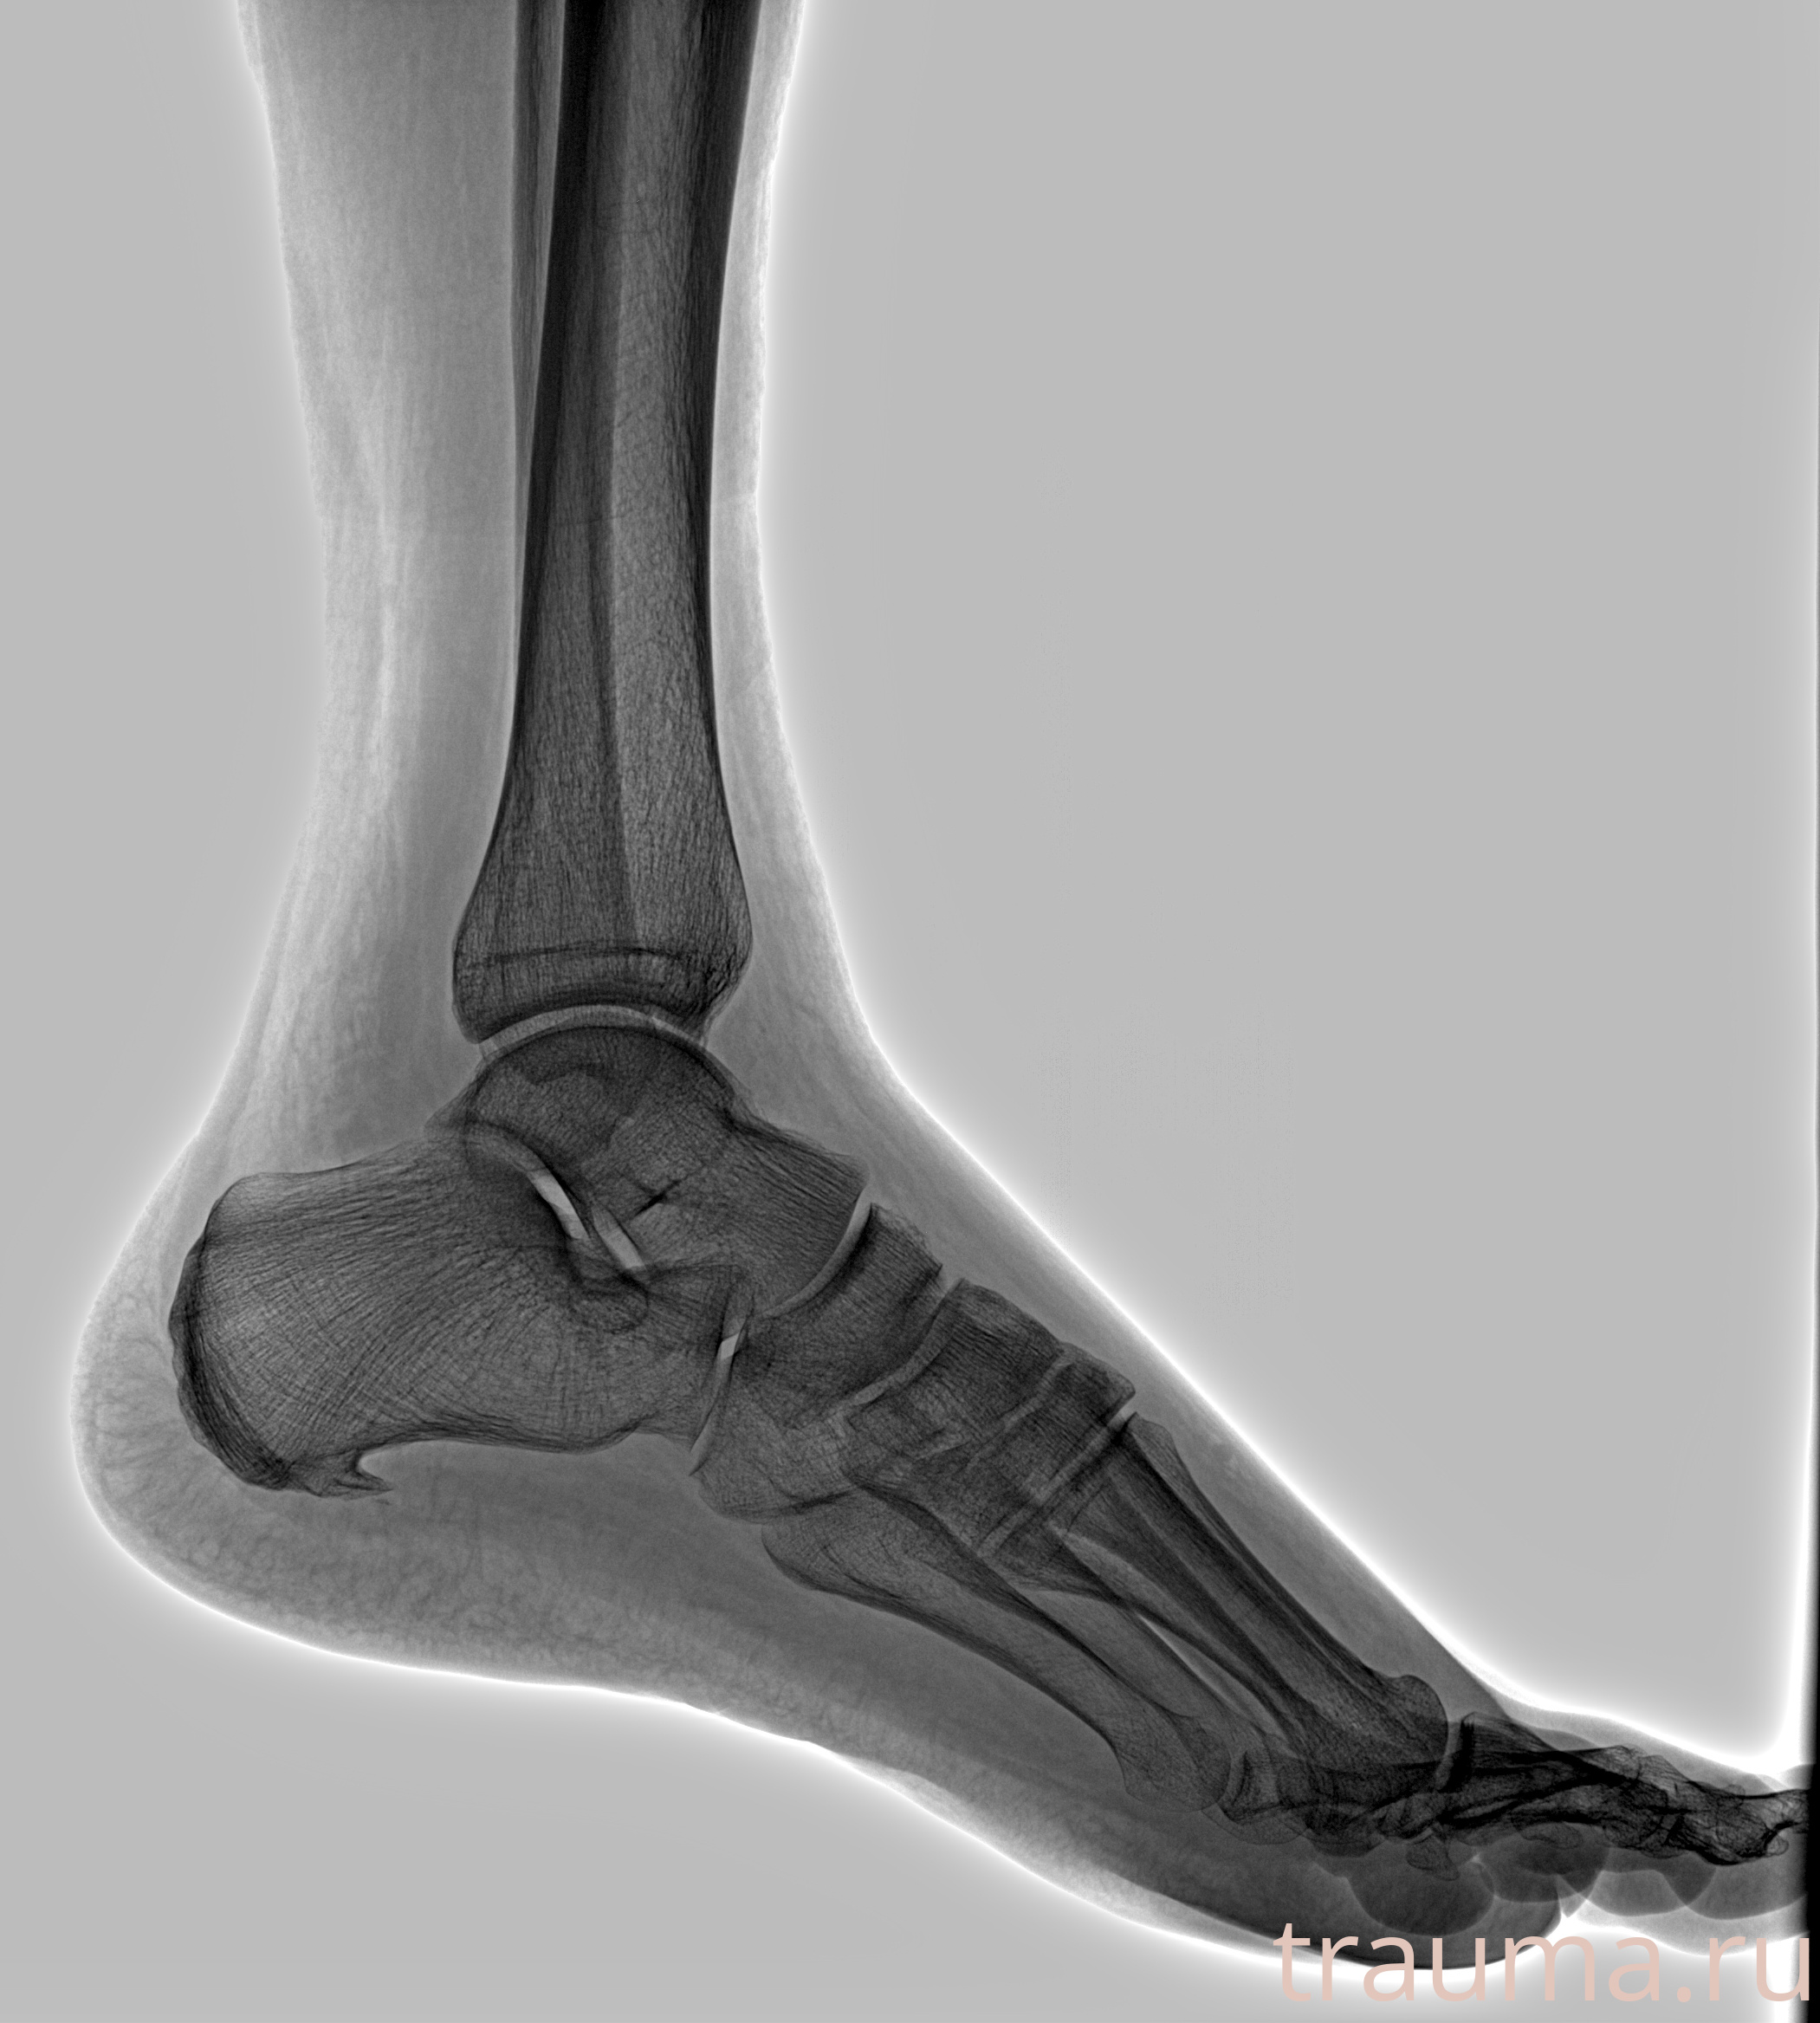

Рентгенограммы

Рентген на дому: по вашему адресу приезжает врач-рентгенолог, травматолог-ортопед с мобильным рентгеновским аппаратом, проводит диагностику травмы или заболевания, делает необходимые рентгенограммы, дает рекомендации по дальнейшему лечению. Получить качественные снимки в домашних условиях возможно благодаря уникальной методике, разработанной МосРентген Центром для института  Склифосовского

Яркость: 1   Контраст: 1   Инвертировать: 0 Увеличение: 1

Перетаскивайте мышь вверх/вниз для контраста, влево/право для яркости. Прокрутка колесом изменяет масштаб. Нажмите Сбросить для возврата к исходному изображению. При увеличении держите мышь в той области, которую хотите рассмотреть.